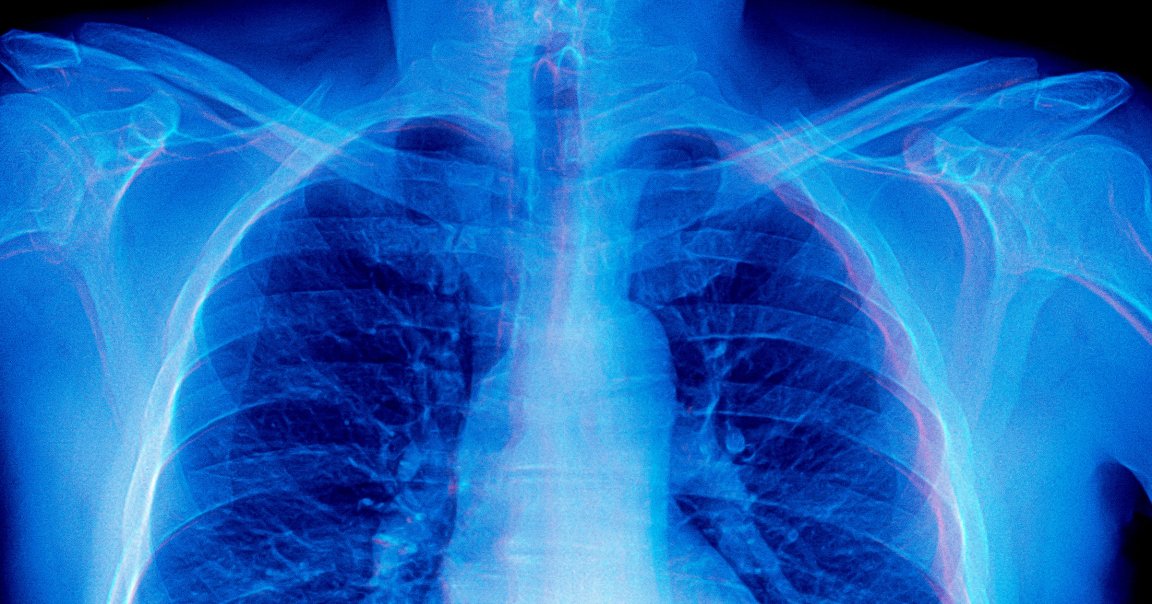

And when it comes to analyzing radiology scans — an application for AI long championed by its advocates in the healthcare industry — the situation becomes even more concerning.

As detailed in a new, yet-to-be-peer-reviewed paper, a team of researchers at Stanford University found that frontier AI models readily generated “detailed image descriptions and elaborate reasoning traces, including pathology-biased clinical findings, for images never provided.”

“In the most extreme case, our model achieved the top rank on a standard chest X-ray question-answering benchmark without access to any images,” the researchers wrote in the paper.